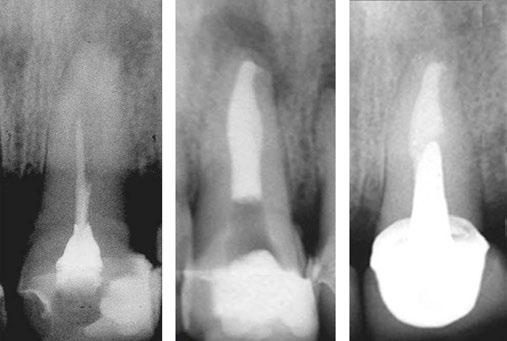

Judy McIntyre, DMD, MS Figure 1: Acutely curved and calcified buccal canal right under upper left premolar crown margin; valuable information for access and management. No. 9 also has a PARL, which was only incidentally captured Figure 2: Large PARL with destruction of the maxillary sinus floor and sinusitis as a result

About 10 years after completing residency, I opened my own practice and invested in a DEXIS CBCT. Initially, I only used it for apicoectomies and retreatments. In time, I began to realize how helpful it was for all my cases. With the 3D-scan information (Figure 1), I could have saved myself some humbling experiences and surprises. Endodontists hate surprises, and we really hate failures! Once I started using my CBCT more frequently, I was able to appreciate things that would have otherwise been intra-op surprises and plan for them prior to starting the procedure. The 3D data allows me to properly assess prognosis, determine the best course of treatment, and plan that treatment with a level of precision that is impossible otherwise.

Figure 3: Second maxillary molar with external root resorption (ERR) with incidentally captured ERR on the lower mandibular first molar as well. When there is one tooth with resorption, be suspicious of other teeth with resorption, especially on younger patients Figure 6: No PARL on PA film. Clear PARL on scan taken with medicament Figures 4 and 5: 4. Mandibular molar with a J-shaped lesion due to endo — not a vertical root fracture. Path of least resistance happens to be through a distal perio pocket, but this is an endo-perio lesion and not a VRF. Incidentally, a mucous retention cyst was captured in the sinus. 5. Healing after bridge removal and retreatment

a realistic prognosis. Unfortunately, not all teeth can be saved. Some are not candidates for retreatment (Figure 11). Without a CBCT scan, it would be easy to attempt these retreatments only to discover the true problem mid-treatment, or worse — to think I had caused one (Figures 10 and 11). This added information not only helps the practitioner, but also provides patients a higher level of confidence and trust in you.

With retreatments, maybe the root canal looks completely fine on a PA or panoramic x-ray, but the patient says that it just doesn’t feel right. A cone beam can often reveal the cause of the patient’s discomfort. This could be that the tooth was perforated, cracked or has an unfilled canal, and the patient is totally justified in feeling like something’s wrong. Or sometimes the scan will show that there is another issue on an adjacent tooth or in the patient’s sinuses (causing their discomfort). When patients sense a problem but are told that there is not one (usually based on 2D radiographs), that’s not a great feeling. Being able to show the patient the CBCT scan and say, “You were right, and here’s the issue,” improves the patient experience.

Figure 7: Planned-for access with the scan info on this extremely calcified canine Figures 8 and 9: 8. Deep distal split with PARL. 9. Missed buccal canal; history of previous RCT, post, crown and apico Figure 10: Retreatment consultation. PA from GD Figure 11: Scan images show a previously existing strip perforation

I’m also changing my treatment plans based on the data from my CBCT. Sometimes I look at a root canal treated PA and presume I know what I will do: a retreatment or an apico. Another recent, poignant case: a lower incisor with a previous RCT and a previous apico (Figure 9). Usually, once a tooth has had an apico, there may not be much left to offer and most of the time, the default is another apico, especially as there was very little room for an implant on the lower anteriors. I scanned the tooth and saw that a whole canal had been missed — twice! The RCT and the apico had left the buccal canal completely untouched. I changed my treatment plan based on this information!